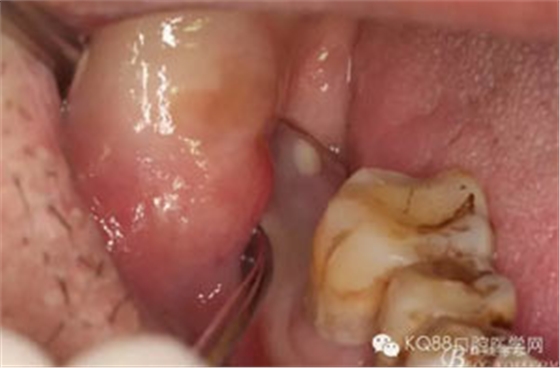

圖1。術(shù)前檢查的口內(nèi)像:48區(qū)域的位置有一瘺口。捫診溢膿。48未萌出。